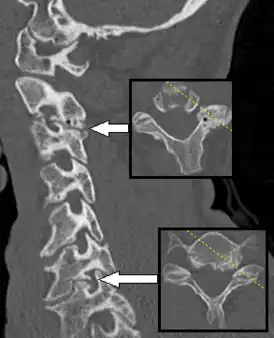

Спондилёз (spondylosis; греч. «spondylos»- позвонок; син. деформирующий спондилёз) — инволюционный процесс постепенного изнашивания и старения анатомических структур позвоночника, сопровождающийся дистрофией наружных волокон передних или боковых отделов фиброзного кольца, выпячиванием его под давлением сохранившего свой тургор мякотного ядра, отложением и оссификацией передней продольной связки и образованием краевых костных разрастаний (остеофитов) вдоль оси позвоночника только по окружности передних и боковых отделов.

При спондилёзе костная ткань суставов разрастается, образуются остеофиты, то есть дополнительная костная ткань (по мере нарастания костный вырост распространяется к соседнему позвонку, тогда как от соседнего позвонка образуется такой же вырост, в некоторых случаях окостенение начинается на уровне межпозвоночного диска). В особо тяжёлых случаях наступает сращение позвонков, от чего страдают сосуды, нервы и мышечная ткань, а также близлежащие органы.